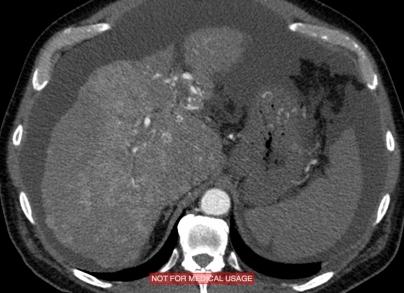

На МР-томограммах отмечается увеличение размеров печени и селезенки. Структура паренхимы печени неоднородная за счет диффузных мелкоузловых гипоинтенсивных участков. В брюшной полости полости определяется умеренное количество свободной жидкости. ЗАКЛЮЧЕНИЕ: мелкоузловой цирроз печени, гепатоспленомегалия, асцит.